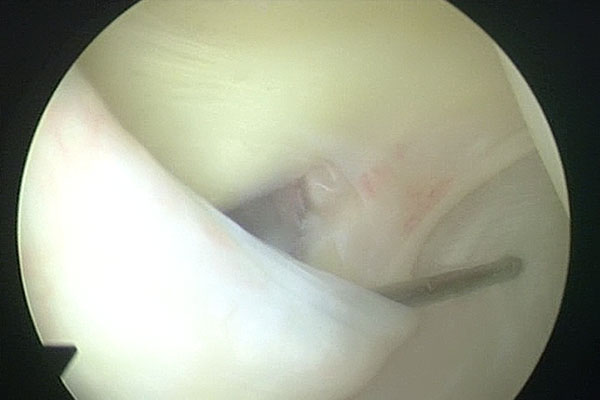

Arthroscopic Management of Baker's CYST